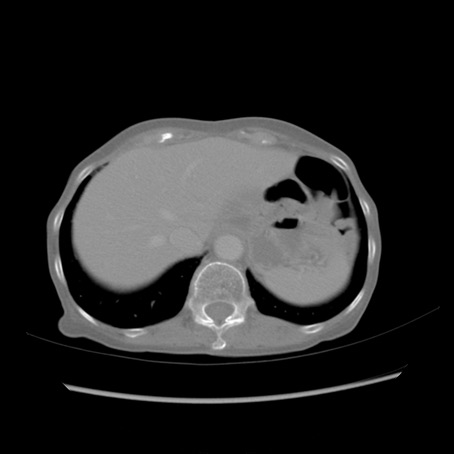

症例25(横断像)

【症例】80歳代女性

【主訴】胸のつかえ感

【現病歴】約9時間前に食後から胸のつかえた感じあり、嘔吐あり、来院。

【既往歴】胃癌(全摘)、胆摘、虫垂炎

【身体所見】心窩部に圧痛あり、反跳痛なし。

【データ】WBC 5700、CRP 0.05